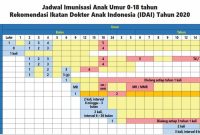

Lebih Cermat pada Susu Anak: Kuatkan Protein, Kurangi Gula!

Pentingnya Pemilihan Susu Pertumbuhan yang Tepat untuk Anak Usia 1–3 Tahun Tumbuh kembang anak sejak dini sangat dipengaruui oleh asupan […]

Stunting Dapat Dicegah dengan MPASI dari Bahan Lokal

Peran Penting MPASI dalam Pencegahan Stunting Berdasarkan data Survei Status Gizi Indonesia (SSGI) tahun 2024, prevalensi stunting di Indonesia masih […]